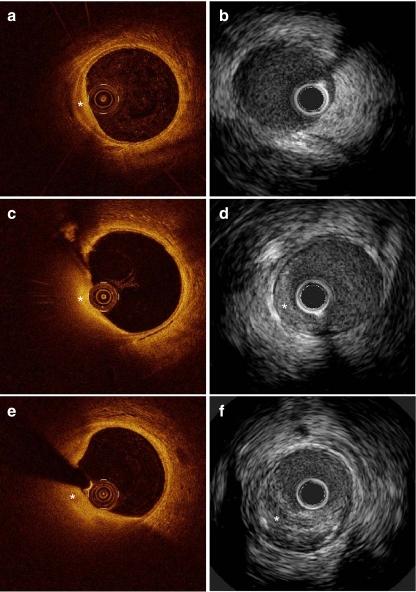

Invasive coronary imaging in animal models of atherosclerosis.